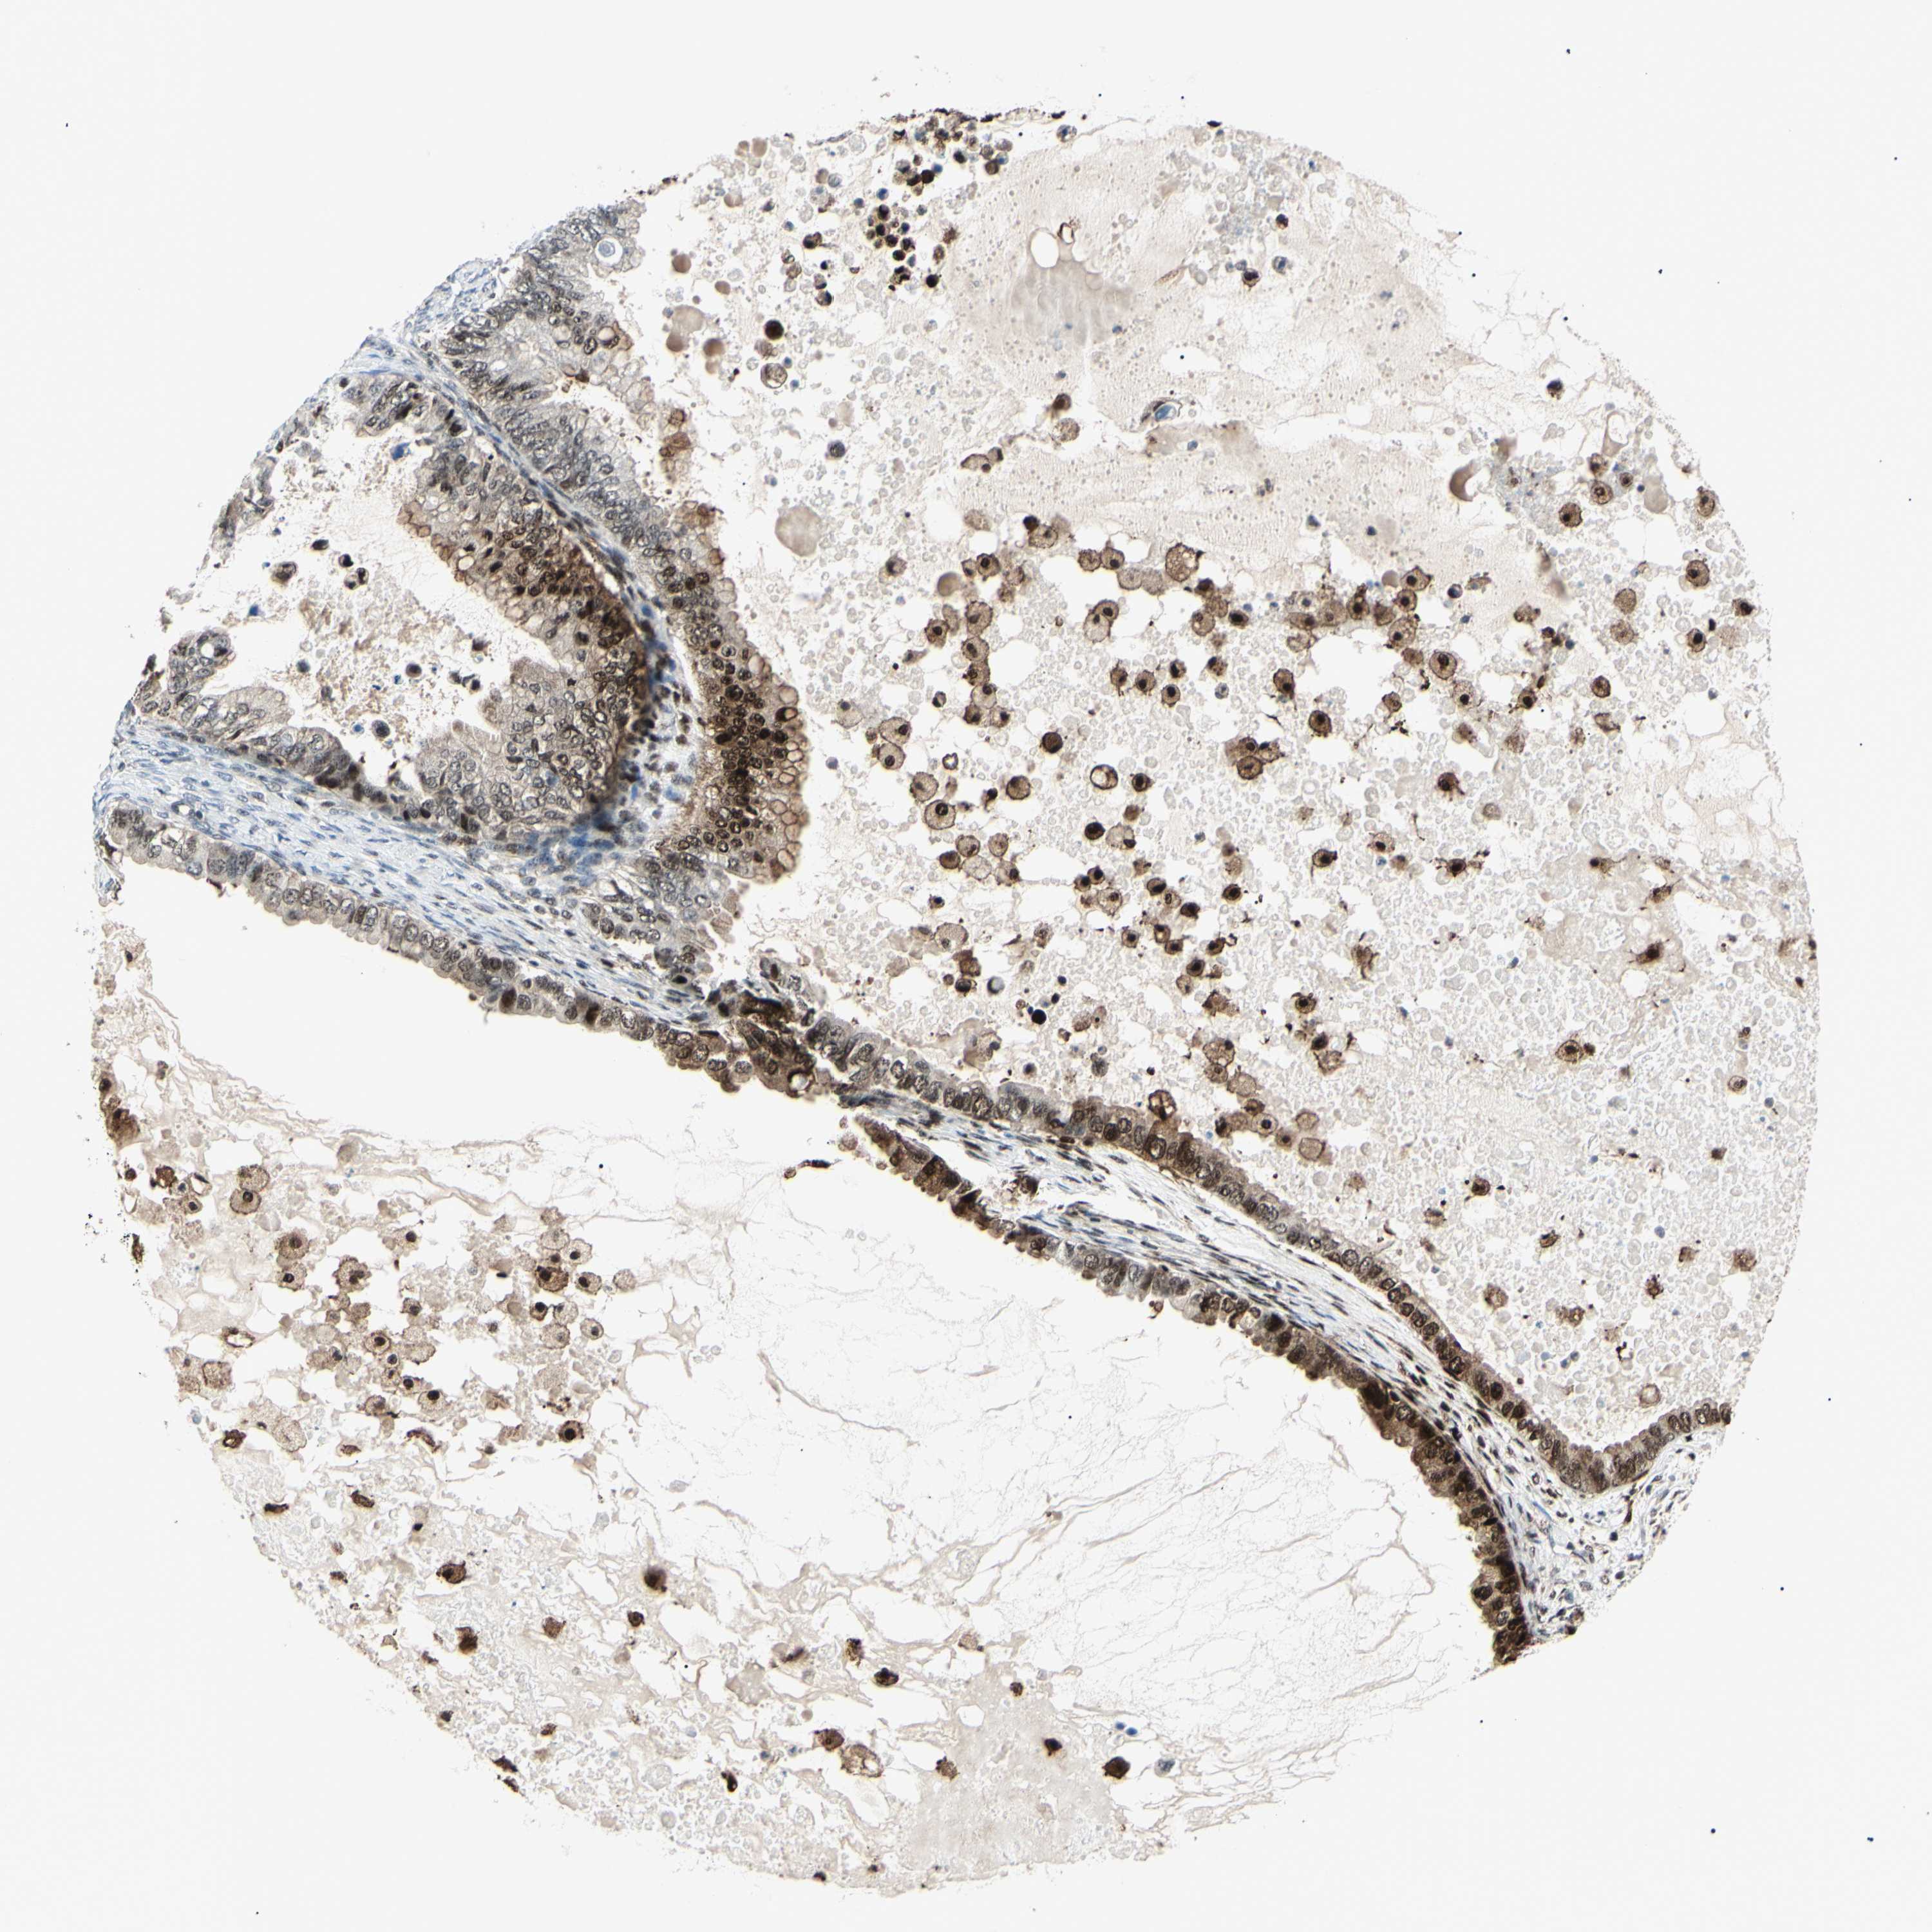

OVARIAN CANCER - Protein expressioni

A mouse-over function shows sample information and annotation data. Click on an image to view it in a full screen mode. Samples can be filtered based on level of antibody staining by selecting one or several of the following categories: high, medium, low and not detected. The assay and annotation is described here.

Note that samples used for immunohistochemistry by the Human Protein Atlas do not correspond to samples in the TCGA dataset.

Antibody stainingi

Antibody staining in the annotated cell types in the current human tissue is reported as not detected, low, medium, or high, based on conventional immunohistochemistry profiling in selected tissues. This score is based on the combination of the staining intensity and fraction of stained cells.

Each image is clickable and will lead to virtual microscopy that enables deeper exploration of all samples and also displays staining intensity scores, fraction scores and subcellular localization as well as patient and tissue information for each sample.

Antibody HPA073656

Staining

High

Medium

Low

Not detected

Cystadenocarcinoma, mucinous, NOS